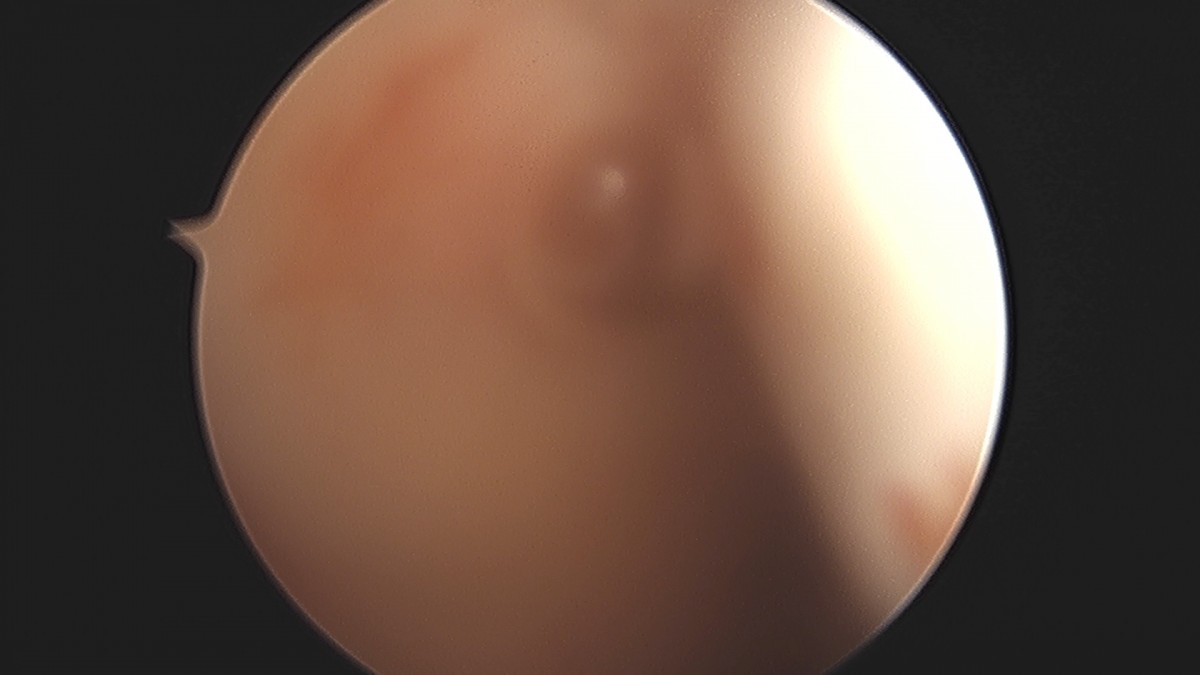

이재상원장님 어깨 석회 제거술 조광O 환자

dae765e4d9ac96aee867c9d6292d8784_1758004693_1483.jpg